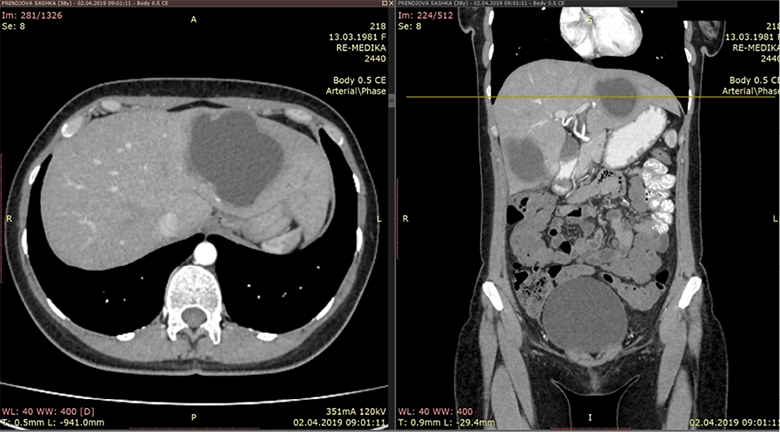

An CT scan of the abdomen was performed and were found two cystic liver formations, also a cystic formation was verified in the pelvis. The native series of the abdominal CT have shown a segment II and IV hepatic per-magna cystic formations with dimensions: No I: 80×60×74 mm (Figure 1) and No. II: 70×60×58 mm (Figure 2). The changes are with a pericystic reaction of a hypodense character. The formation in the second hepatic segment had a visible mass effect on the stomach. In post contrast series, cystic liver formations were shown as hypodense, hypovascular structures with a clearly expressed contrast accumulation in the cystic membrane and with a demarcation of the pericystic reaction. Per magna cystic formation with hypodense character was also detected at the level of the small pelvis, retrouterine, in the Douglas space, with dimensions of 93×90×62 mm (Figure 3). The cyst has a clearly expressed mass effect on surrounding organ structures. Utter in the AVF pressed to the left. The liver cystic formations were with characteristics of Ehcinococcal cyst but with no serological verification.

Figure 1. Liver segmet II permagna cystic formation

Figure 2. Segment IV hepatic cystic formation